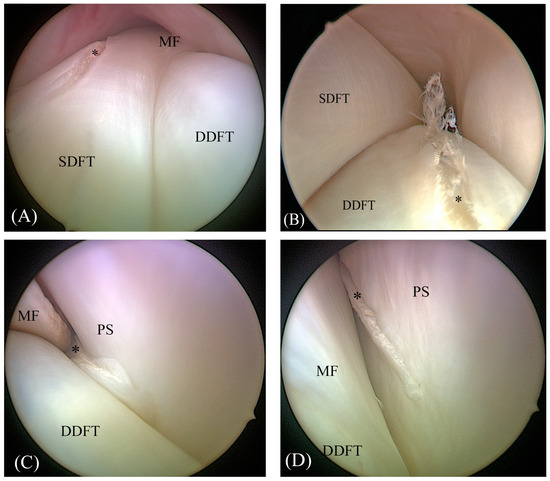

2.2. Tenoscopic Procedure